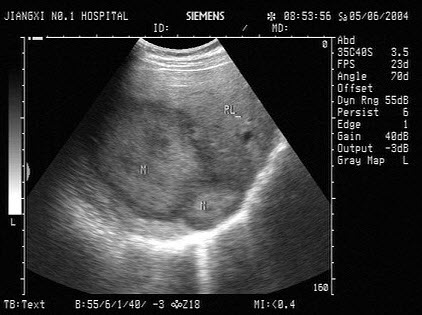

某患者自诉乳腺可触及一包块,光滑可移动,超声图像如图,诊断为()

A.纤维瘤

B.囊肿

C.乳腺癌

D.小叶增生

E.乳腺导管扩张